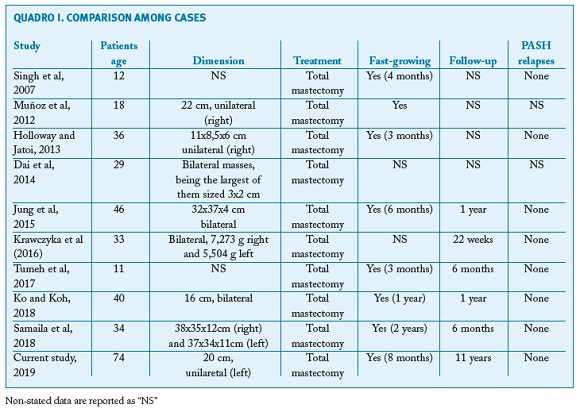

In reviewing literature, we found 9 other cases of PASH treated through mastectomy (Table 1).

Ko and Koh (2018)11 reported the case of a 40-year-old woman who developed a progressive bilateral breast enlargement for approximately 1 year. Mammography was inconclusive, but breast ultrasonography (US) showed a heterogenous, hypoechoic, and circumscribed mass measuring approximately 16 cm at the largest diameter in each breast. A bilateral mastectomy was performed because of the extent of the lesions and pain symptoms. The microscopic of surgical specimens led to the diagnosis of PASH, supported by immunohistochemical studies. The postoperative period was uneventful for 1 year of following-up.

Additionally, Samaila et al (2018)12 reports the case of a 34-year-old woman with a 2 year history of rapid progressive painless bilateral enlargement of the breasts. The examination revealed bilateral nontender giant breasts extending to the umbilical area with masses which were not attached to overlying skin and Grade 2 pressure ulcers on the lateral posterior breast aspects bilaterally. A bilateral mastectomy was performed and it revealed giant PASH which was confirmed by the positive immunohistochemical reactivity for CD34 and vimentin. No other breast pathologies were seen with extensive sectioning.

According to Tumeh et al (2017)13, a 11-years old patient presented a history of excessive breast growth in 3 months. She was assessed by the mastology team and released for a reduction surgery, however, during the intraoperative period it was observed that the breast tissue presented an anomalous appearance, diffusely infiltrated, white-grayish and fibroelastic, without cleavage planes. It was decided to perform a total mastectomy. The anatomopathological study showed absence of malignancy and the immunohistochemical study showed a profile compatible with bilateral PASH.

Krawczyka et al (2016)14 shows a case of a 33-year-old woman at 14 weeks of her first pregnancy, presenting a massive bilateral breast enlargement. Bilateral diagnostic biopsies showed diffuse PASH of both breasts, plus an ultrasound revealed increased breast density with pronounced lymphoedema, without local lymphadenopathy. Due to rapid progression of the macromastia, a bilateral skin-sparing mastectomy with immediate reconstruction was performed at 16 weeks of pregnancy. Bilateral mastectomy specimens were removed. Histological tissue examination revealed typical characteristics of PASH-like stromal hyperplasia The further course of pregnancy was uneventful.

The fifth case analyzed, published by Jung et al (2015)15, presents a patient with a bilateral diffuse lesion, in which the histologic examination of the specimens after mastectomy showed characteristic features of diffuse PASH. After a 12-month follow-up the patient didn’t have any relapses.

Similarly, the case reported by Dai et al (2014)16 presents a rare case of diffuse tumorous PASH involving bilateral breasts, clinically similar to a malignant lesion. The patient presented a one-year history of bilateral breast enlargement and asymmetry. Physical examination revealed multiple palpable nodule in bilateral breasts. Biopsy of the breast nodules demonstrated a diagnosis consistent with PASH. The stromal cells were positive, at the immunohistochemical staining, for estrogen receptor (ER) and progesterone receptor (PR) and negative for CD31, supporting the diagnosis of PASH. A bilateral mastectomy was performed, with immediate reconstruction.

Holloway and Jatoi (2013)17 reported the case of a 3-month history of progressive, rapid enlargement of the right breast. The diagnosis was PASH, with no evidence of malignancy. Besides, the growth was very rapid. The patient underwent a total mastectomy and immediate breast reconstruction. The patient had an excellent clinical and cosmetic outcome.

Muñoz et al (2012)18 presents two case reports: two adolescents (13 and 18 years old) in which rapidly growing masses demonstrated a histopathological result of PASH. Both masses were rapidly growing so they needed to be removed: in the former case through an excision, in the latter through a mastectomy. The study doesn’t refer relapses.

The oldest case within our literature research, reported by Singh et al (2007)8, corresponds to a 12-year-old girl with a 4-month history of bilateral breast enlargement. Right breast biopsy revealed PASH. Initially, surgical excision was performed. However, the lesion was resistant to surgical excision and it required bilateral mastectomies.

The current study reports the case of the oldest patient so far, suggesting that even in menopause PASH should be a differential diagnosis in women with breast tumor. Menopause seems not to change PASH behavior, since the speed of growth was similar to the cases of younger women. Furthermore, a long follow-up (11 years), without recurrence or other breast pathoogy suggests that PASH probably does not have breast cancer risk even in menopausal women.